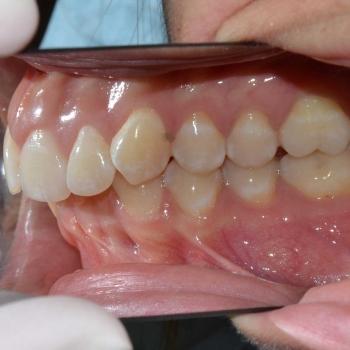

Judit az alsó és felső fogív torlódása, illetve ennek a problémának a megoldása kapcsán keresett fel rendelőmben. Már az első vizsgálat alkalmával fény derült arra, hogy a torlódáson kívül egyéb harapási eltérésekkel is számolni kell: mélyharapással, illetve Angle II-es harapási eltéréssel. Ennek megfelelően Judit kezelési tervében több lehetőséget is felvázoltam a problémák maradéktalan megoldására, ám ezek sajnos foghúzást és/vagy állcsont műtétet igényeltek volna. Ezeket a beavatkozásokat Judit nem vállalta, így döntését tiszteletben tartva kialakítottam egy olyan kezelési tervet, amellyel a legkevesebb kompromisszum megkötése mellett a lehető legtöbb feltárt problémára megoldást tudtam nyújtani.

Közös döntés eredményeként tehát egy kizárólag az esztétikára fókuszáló fogszabályozási tervet valósítottunk meg, melyhez a prémium önligírozó kerámia fogszabályozót és az alsó metszőfogak stripelését használtuk fel. A kezelés eredményeként mindkét fogívben megszűnt a torlódás, illetve a mélyharapás is. Annak érdekében, hogy az elért eredmény a lehető legtartósabb legyen a kivehető retenciós fólián kívül az alsó fogívre fix retainert helyeztünk fel.